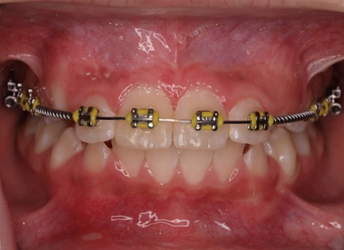

Qúa trình chỉnh nha kéo răng cửa mọc ngầm hoàn tất

Hình 5: Minh họa phẫu thuật lấy răng thừa kết hợp với chỉnh nha ở một bé trai 9 tuổi